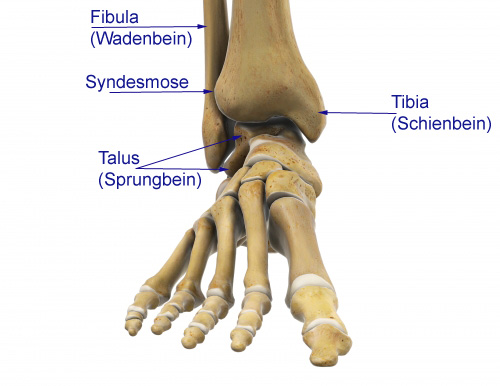

Bei einer Talusnekrose wird das Sprungbein (Talus) nicht mehr ausreichend durchblutet und stirbt ab. Das Sprungbein ist ein Fußknochen, das zusammen mit Schienbein (Tibia) und Wadenbein (Fibula) das obere Sprunggelenk (OSG) bildet. Schien- und Wadenbein umfassen dabei das Sprungbein passgenau wie eine Zange - man spricht auch von der Sprunggelenksgabel (Malleolengabel).

Funktion und Anatomie des Sprungbeins (Talus)

Der Talus nimmt unter den Fußknochen eine Sonderstellung ein. Das Sprungbein besitzt keine Sehnen und keinen Muskelansatz. Ausschließlich Bänder an benachbarten Knochen halten das Sprungbein in seiner Position. Eine zusätzliche Durchblutung und Versorgung des Knochengewebes durch Sehnenansätze existiert nicht.

Zwischen Taluskörper und Taluskopf liegt der Talushals. Er bildet das Dach des Sinus tarsi, eines Knochentunnels zwischen Fersenbein (Calcaneus) und Talus. Der Sinus tarsi dient als Eintrittsstelle für Blutgefäße in den Talus. Die Durchblutung wird überwiegend über diese Gefäße sichergestellt.

Oberhalb des Talus mit der aufliegenden Sprunggelenksgabel liegt das obere Sprunggelenk (OSG). Distal grenzt der Talus an das Fersenbein (Calcaneus), mit dem er über das talocalcaneare Gelenk verbunden ist. Dieses Gelenk bildet den hinteren Teil des unteren Sprunggelenks. Nach vorne steht der Taluskopf mit dem Kahnbein (Os naviculare) in gelenkiger Verbindung. Hier sind drei Gelenkflächen an der Gelenkbildung beteiligt. Durch diese besondere Anatomie ist ein Großteil der Talusoberfläche mit Knorpel bedeckt.